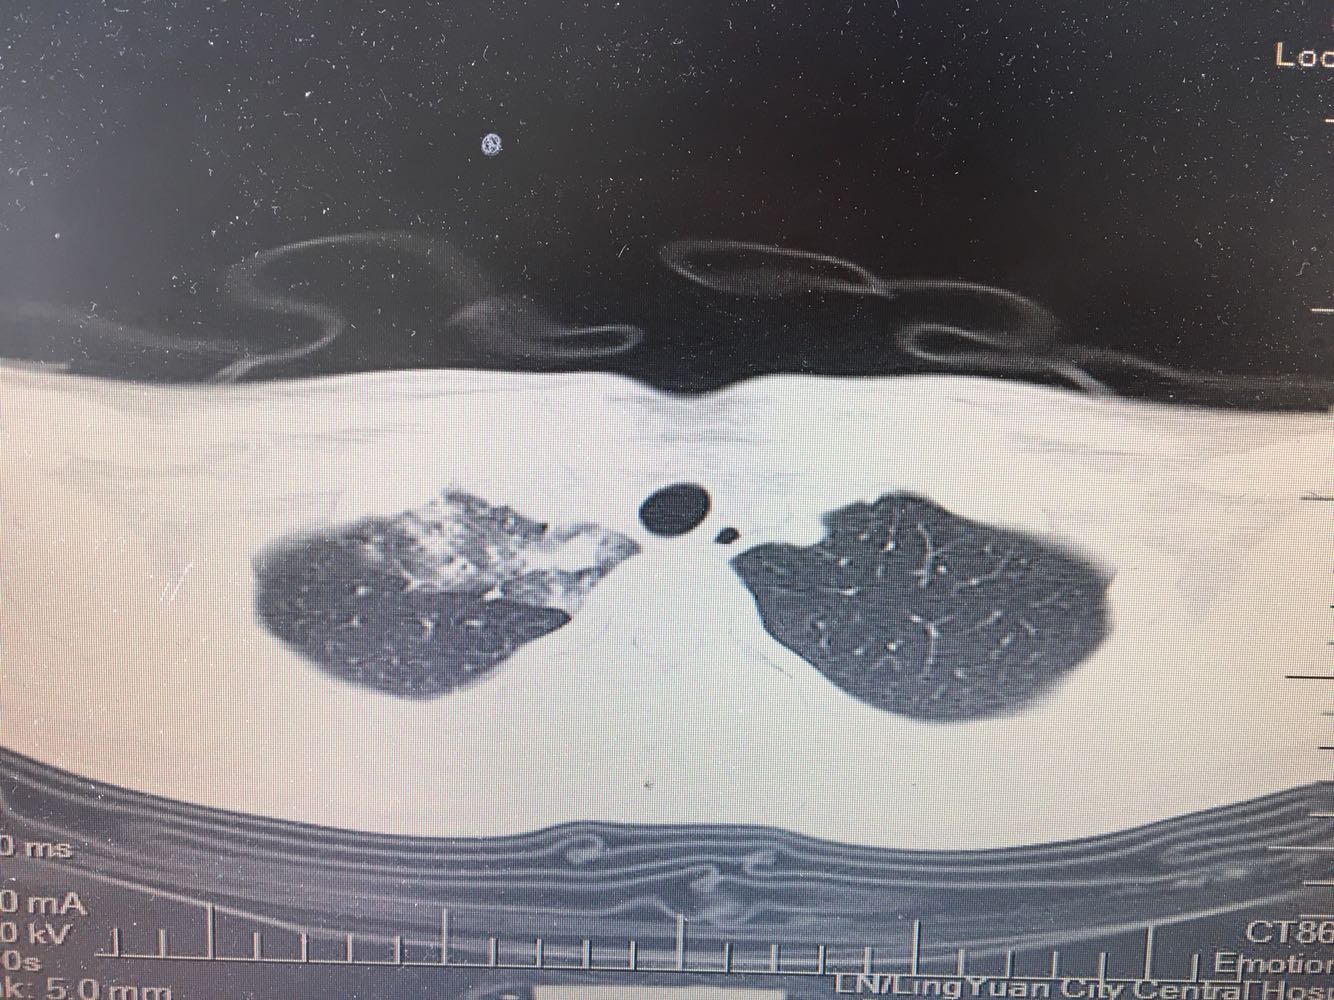

女,26岁,咳嗽1周,咳痰不畅,咽喉痒,口服阿莫西林无好转,昨日发热,体温38.5摄氏度,于门诊查肺CT后以肺炎收入院,病来无盗汗,无咳血,无消瘦及乏力,无头痛,无肢体酸痛,饮食睡眠可,二便正常

神清言明,咽部无充血,扁桃体不大,双肺呼吸音清,无罗音,服软无压痛。

支原体抗体1:160,结核抗体弱阳性。支原体肺炎个别可见上叶病变,该患无结核中毒症状,考虑支原体肺炎可能性大,但肺尖为结核好发部位,需要抗炎治疗后复查观察疗效。